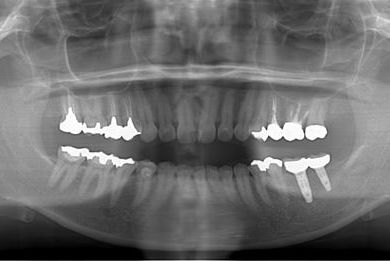

抜歯即日スピードインプラント治療+セラミック治療+歯肉歯槽骨整形術

| 治療方針 | 左下欠損部と保存不能の歯を抜歯し、インプラント治療にて機能的・審美的回復を行う。 | ||||||||||||||||||||||||||||||||

| 治療内容 | インプラント2本(抜歯即日スピードインプラント)、ハイブリッドセラミッククラウン2本、歯肉歯槽骨整形術 | ||||||||||||||||||||||||||||||||